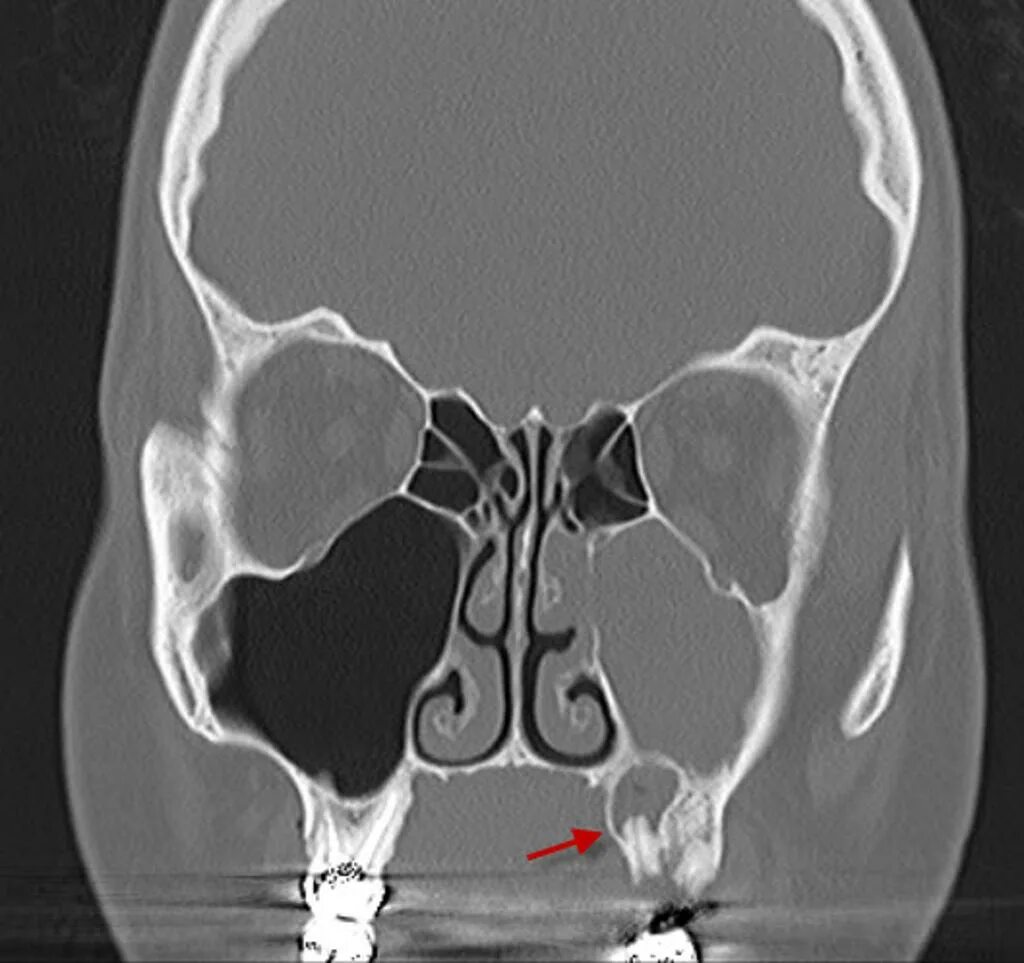

Синусит на кт